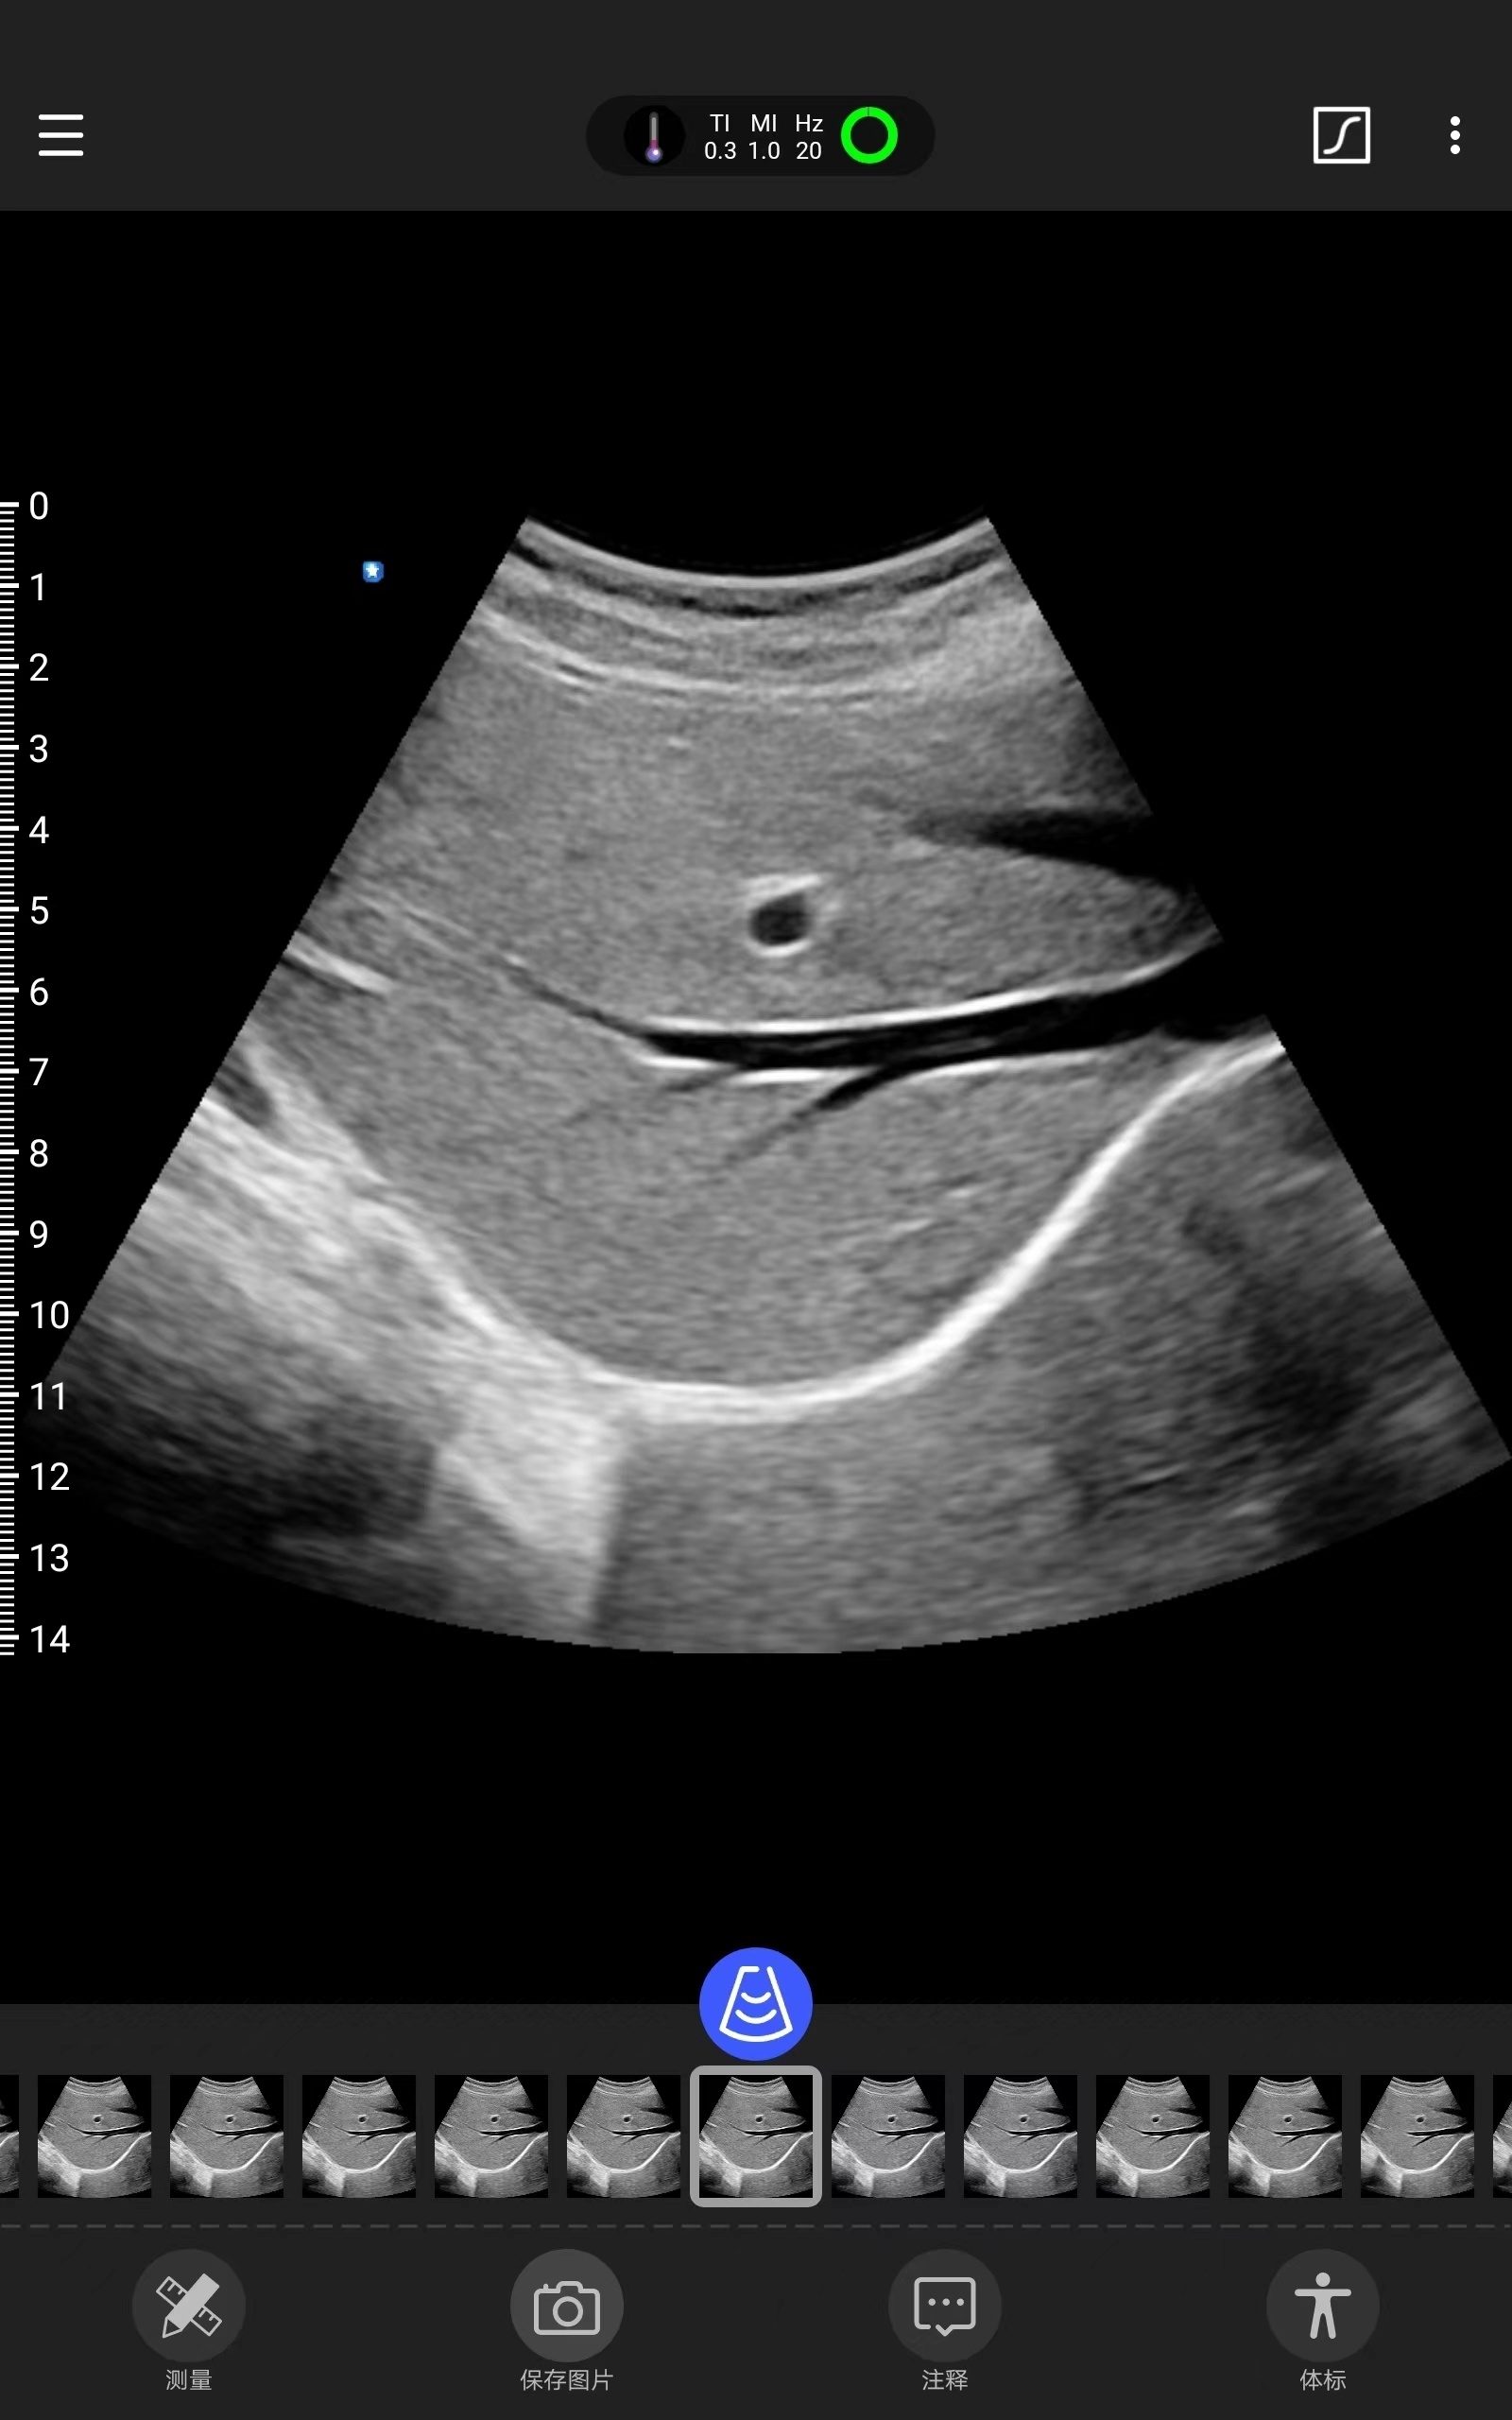

Galería de demostración

|